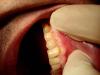

dantist-ya Опубликовано 14 мая, 2013 Поделиться Опубликовано 14 мая, 2013 (изменено) Всем доброго времени суток!!! Помогите с планом лечения. Пац уезжает в Австралию на пмж, приехать сможет как минимум через три года. КД очень глубокий, поражены все зубы,какие то меньше,другие больше. Прикус ортогнатический. За качество фото извиняйте,фотал на телефон.Стоит ли одевать коронки на эти зубы? Или же пока эндодонтия ,реставрация и в добрый путь на 3 года? Работаю без кофера,а кд уже под десной. Изменено 14 мая, 2013 пользователем dantist-ya Ссылка на комментарий